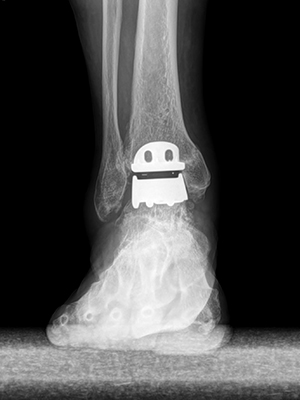

발목인공관절 Total ankle replacement arthroplasty

발목인공관절은 말기 발목 관절염의 수술적 치료 중 하나입니다. 관절염이 심하게 진행되어 관절의 기능을 잃은 연골을 깎아 인공관절을 삽입하는 치료입니다. 통증은 완화시켜주고 발목이 제 기능을 할 수 있게 도움을 주는 치료법입니다.

말기 발목관절염으로​ 뼈의 간격이 전체적으로 소실됨​​

​손상된 발목관절을 제거하고​ 인공관절을 삽입하여​ 발목 관절의 움직임 유지​

발목 인공관절은 발목 관절의 뼈를 10mm 정도 깎아내어 뼈의 표면에 인공관절을 삽입하여 발목 연골 역할을 하게하는 고난도 수술입니다.​

• 수술 전​​

• 수술 후​​

SNU서울병원 발목인공관절 수술 사례

• 수술전​​

• 수술후​